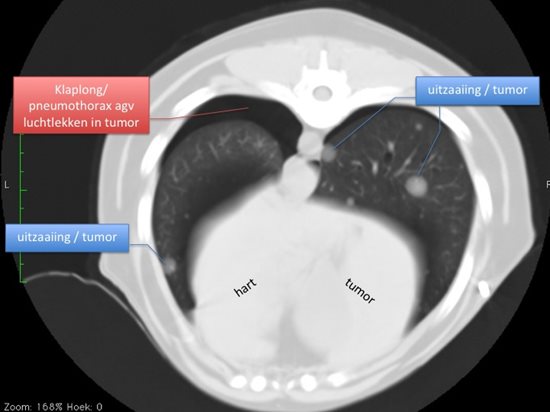

bijv. voor het zoeken naar uitzaaiingen van tumoren in de longen: op een röntgenfoto zijn ze pas zichtbaar vanaf 5-6 mm, terwijl op een CT-beeld ze reeds zichtbaar zijn vanaf 3mm.